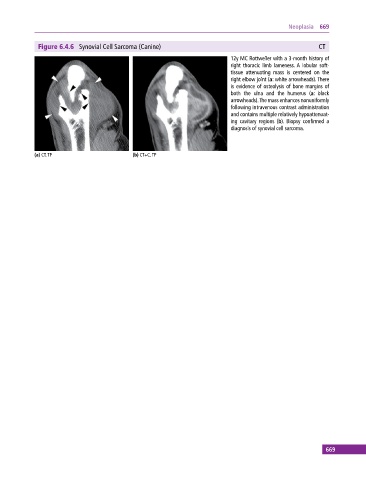

Figure 6.4.6 Synovial Cell Sarcoma (Canine) CT

12y MC Rottweiler with a 3‐month history of

right thoracic limb lameness. A lobular soft‐

tissue attenuating mass is centered on the

right elbow joint (a: white arrowheads). There

is evidence of osteolysis of bone margins of

both the ulna and the humerus (a: black

arrowheads). The mass enhances nonuniformly

following intravenous contrast administration

and contains multiple relatively hypoattenuat-

ing cavitary regions (b). Biopsy confirmed a

diagnosis of synovial cell sarcoma.

(a) CT, TP (b) CT+C, TP